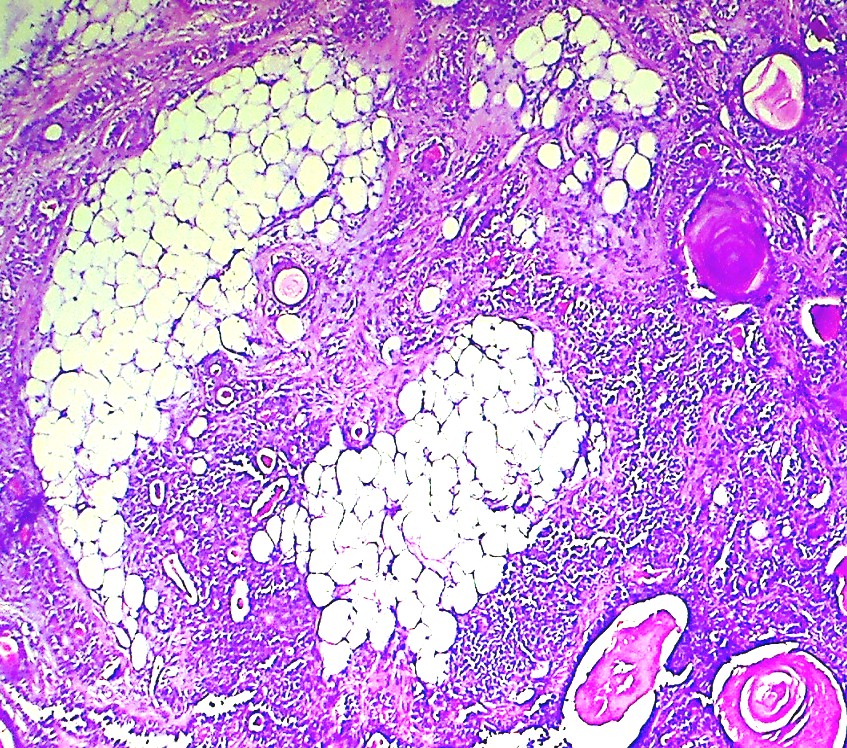

Pathology of Pleomorphic Adenoma Pathology Made Simple Malignant Pleomorphic Adenoma Pathology Outlines Carcinoma ex pleomorphic adenoma is an epithelial malignant neoplasm arising from a primary or recurrent pleomorphic adenoma and. Pleomorphic adenomas are benign ‘mixed’ tumors that consist of varying proportions of epithelial and mesenchymal elements. Pleomorphic adenoma (pa) is the most common salivary gland neoplasm, and its diagnosis is straightforward in the majority of cases. Malignant cases arising from pleomorphic adenoma. Malignant Pleomorphic Adenoma Pathology Outlines.

Pathology of Pleomorphic Adenoma Pathology Made Simple Malignant Pleomorphic Adenoma Pathology Outlines Benign adnexal tumor of the skin composed of mesenchymal and sweat gland components. Malignant cases arising from pleomorphic adenoma (am j clin pathol 2011;136:793) intracapsular carcinoma ex. Pleomorphic adenoma (pa) is the most common salivary gland neoplasm, and its diagnosis is straightforward in the majority of cases. Carcinoma ex pleomorphic adenoma is an epithelial malignant neoplasm arising from a primary. Malignant Pleomorphic Adenoma Pathology Outlines.